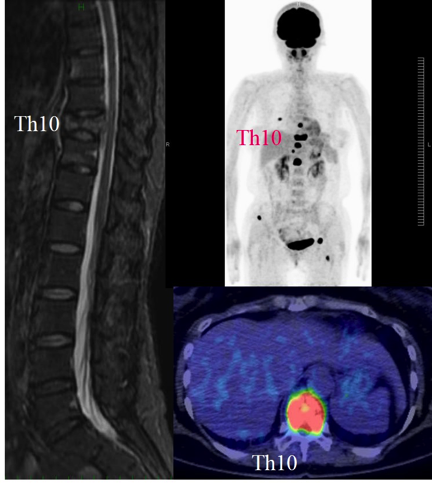

a3f1e84f-s.jpg。骨粗鬆症性椎体骨折に対する脊柱再建術 | 成尾整形外科病院。胸椎・腰椎の疾患 | 聖マリアンナ医科大学 横浜市西部病院。【送料込】 砕米24キロ 割れた米 飼料米 くず米 エサ米 鳥の餌。